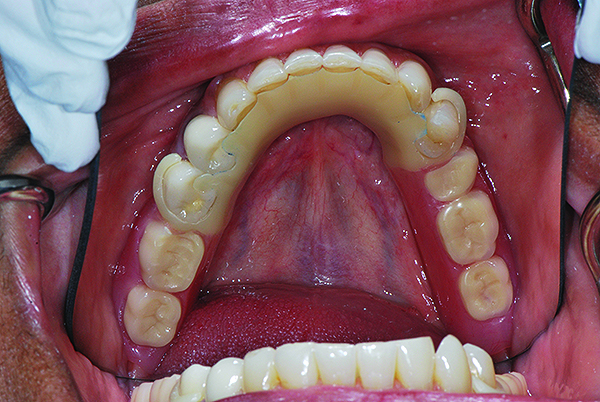

After the denture wax try-in appointment and patient approval, the RPDs were processed and inserted, and necessary clinical adjustments were made (Figure 11, Figure 12, Figure 13)

Fig 12. Occlusal view of maxillary RPD at time of insertion.

Figure 12